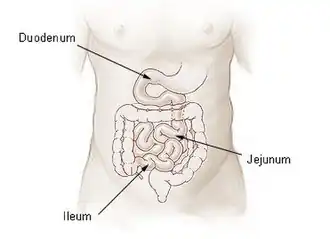

By location

Intestinal atresia may be classified by its location. Patients may have intestinal atresia in multiple locations.[6]

- Duodenal atresia – malformation of the duodenum, part of the intestine that empties from the stomach, and first section of the small intestine

- Jejunal atresia – malformation of the jejunum, the second part of the small intestine extending from the duodenum to the ileum, that causes the jejunum to block blood flow to the colon [7]

- Ileal atresia – malformation of the ileum, the lower part of the small intestine

- Colon atresia – malformation of the colon

Malformations may also occur along multiple portions of the intestinal tract; for instance a malformation that occurs along or spans the length of the jejunum and the ileum is termed jejunoileal atresia.[5][3]